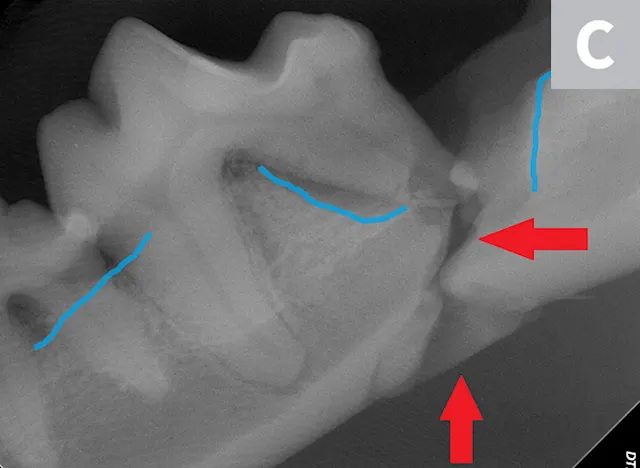

A complete oral examination confirmed stage 4 periodontal disease of numerous teeth (ie, first through fourth maxillary premolars, all maxillary molars, both maxillary canines, all remaining incisors). Dental radiographs confirmed bilateral mandibular fractures at the mesial root of the right mandibular first molar and distal root of the left mandibular first molar (Figures 1 and 2).

Preoperative intraoral dental radiographs of the right (A and B) and left (C) mandibular first molars. There is marked alveolar bone loss secondary to periodontal disease (blue lines), as well as pathologic, iatrogenic mandibular fractures (arrows).